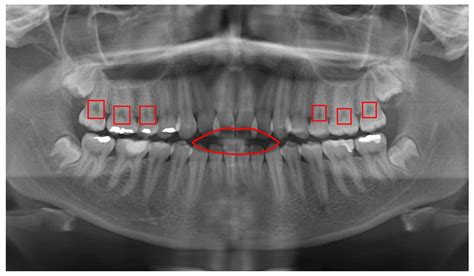

In the realm of dental diagnostics, the panoramic X-ray stands as a pivotal tool, offering a comprehensive view of the oral and maxillofacial region. This imaging technique provides dentists and oral surgeons with a detailed, wide-angle image of the teeth, jaws, temporomandibular joints, and surrounding structures. The panoramic X-ray is invaluable for detecting a range of dental issues, from impacted teeth and jaw disorders to tumors and bone abnormalities. Its ability to capture a broad area in a single image makes it an essential component of modern dental practice, enhancing diagnostic accuracy and treatment planning.

A panoramic X-ray, also known as a panoramic radiograph, is a type of dental imaging that captures a wide view of the upper and lower jaws, teeth, sinuses, and surrounding bone structures. Unlike traditional intraoral X-rays, which focus on individual teeth or small sections of the mouth, a panoramic X-ray provides a comprehensive overview. This makes it particularly useful for identifying issues that may not be visible with more localized imaging techniques.

Interpreting panoramic X-ray results requires a trained eye and a thorough understanding of dental anatomy. Dentists and oral surgeons use these images to identify a range of issues, from impacted teeth and jaw disorders to tumors and bone abnormalities. Some of the key elements that are assessed in a panoramic X-ray include:

• Teeth: The dentist examines the teeth for signs of decay, fractures, or other issues. Impacted teeth, such as wisdom teeth, can also be identified.

• Jaws: The jawbones are assessed for signs of abnormalities, such as fractures, infections, or tumors. The temporomandibular joints (TMJ) are also evaluated for signs of disorders.

• Sinuses: The sinuses are checked for signs of infection or other issues that may affect dental health.

• Bone Structure: The overall bone structure is evaluated for signs of abnormalities, such as cysts, tumors, or bone loss.